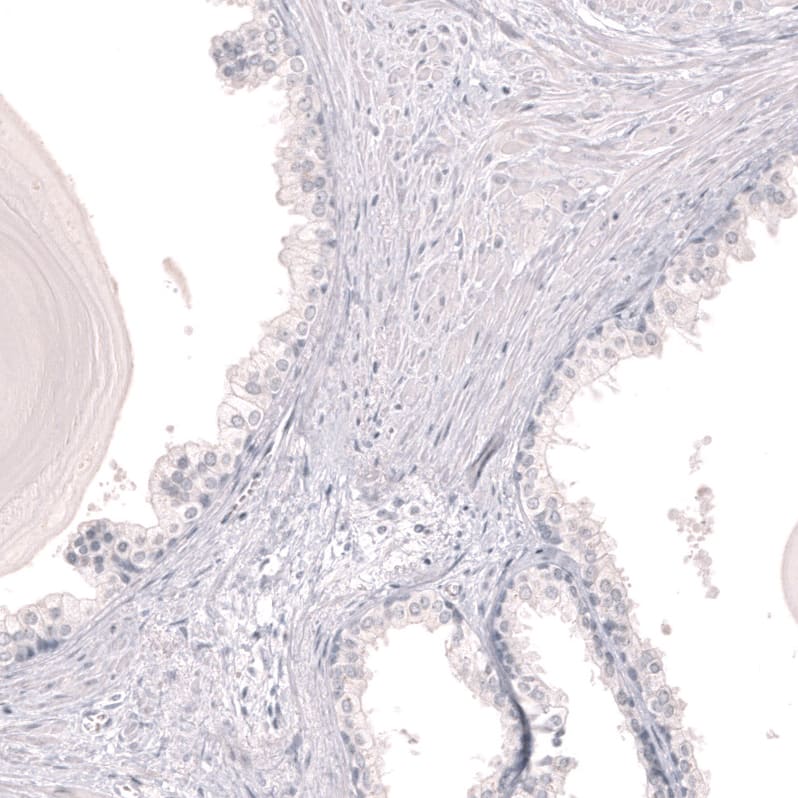

Staining of human prostate shows no positivity in glandular cells as expected.